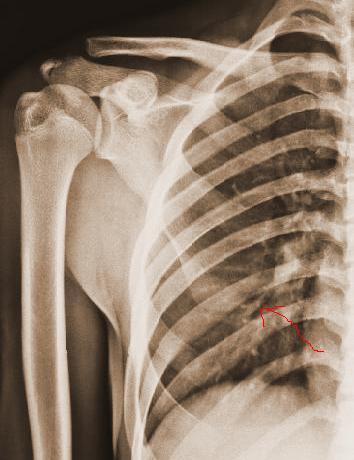

右肩胛骨下角骨折。

开始我发了正常报告,结合侧位透视才发现骨折!如果是自己亲自照就好了,那匪徒的刀法太好了,砍的太整齐。

刀法不只是好,简直堪称绝妙,若非有透视,我绝认为是肺纹.

同志们!老师们!这个病例的确太难了,真的很像肺纹理。我第一次还下正常报告,幸运还没发出去啊!透视了才下骨折。

这绝对是骨折!

诊断这种片子,只有结合临床。